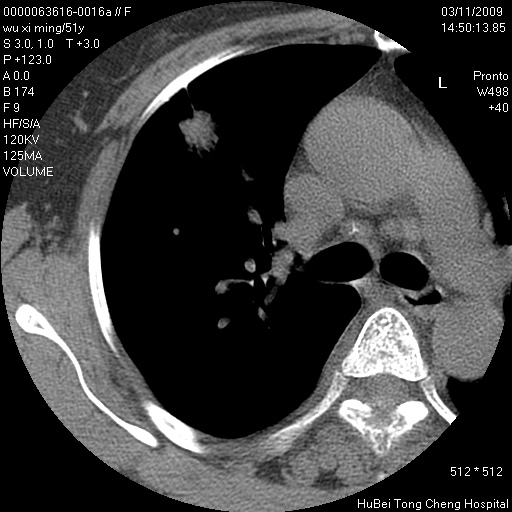

右肺周围型肺癌伴肺内转移信胸椎转移

支持--右肺周围型肺癌---胸椎转移

支持--右肺周围型肺癌---胸椎转移。

支持右上肺肺癌并胸椎转移

有周围性肺癌胸椎转移

右肺周围型肺癌伴肺内转移及胸椎转移。已无手术机会。